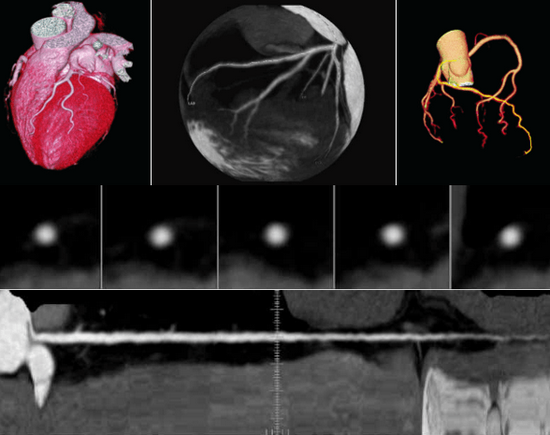

Aheart-Coronary angiography

Innovative ECG gated trigger and real-time dynamic tube current modulation to achieve low dose HD coronary angiography, clearly show the fine structure of stents and lesions.